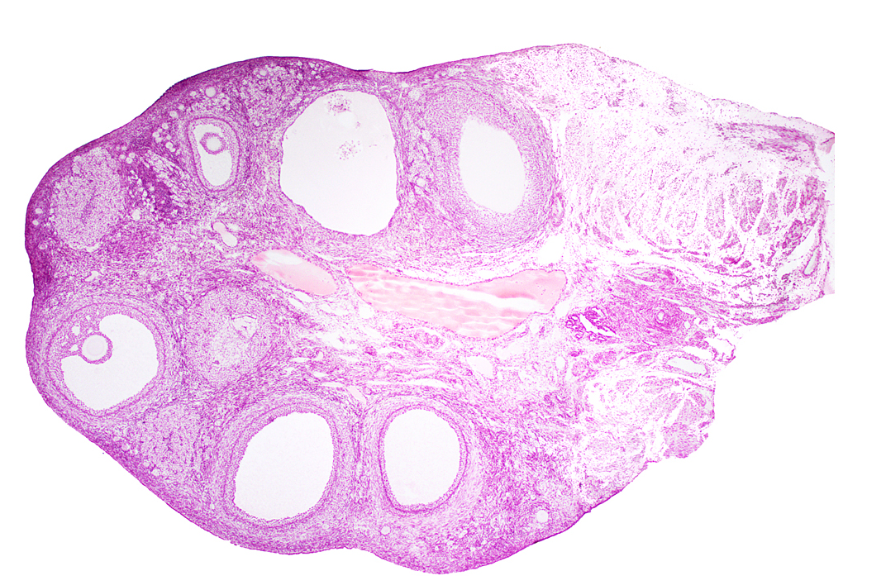

ovary (sagittal section)

cortex

corpus luteum

mature tertiary follicle

antrum